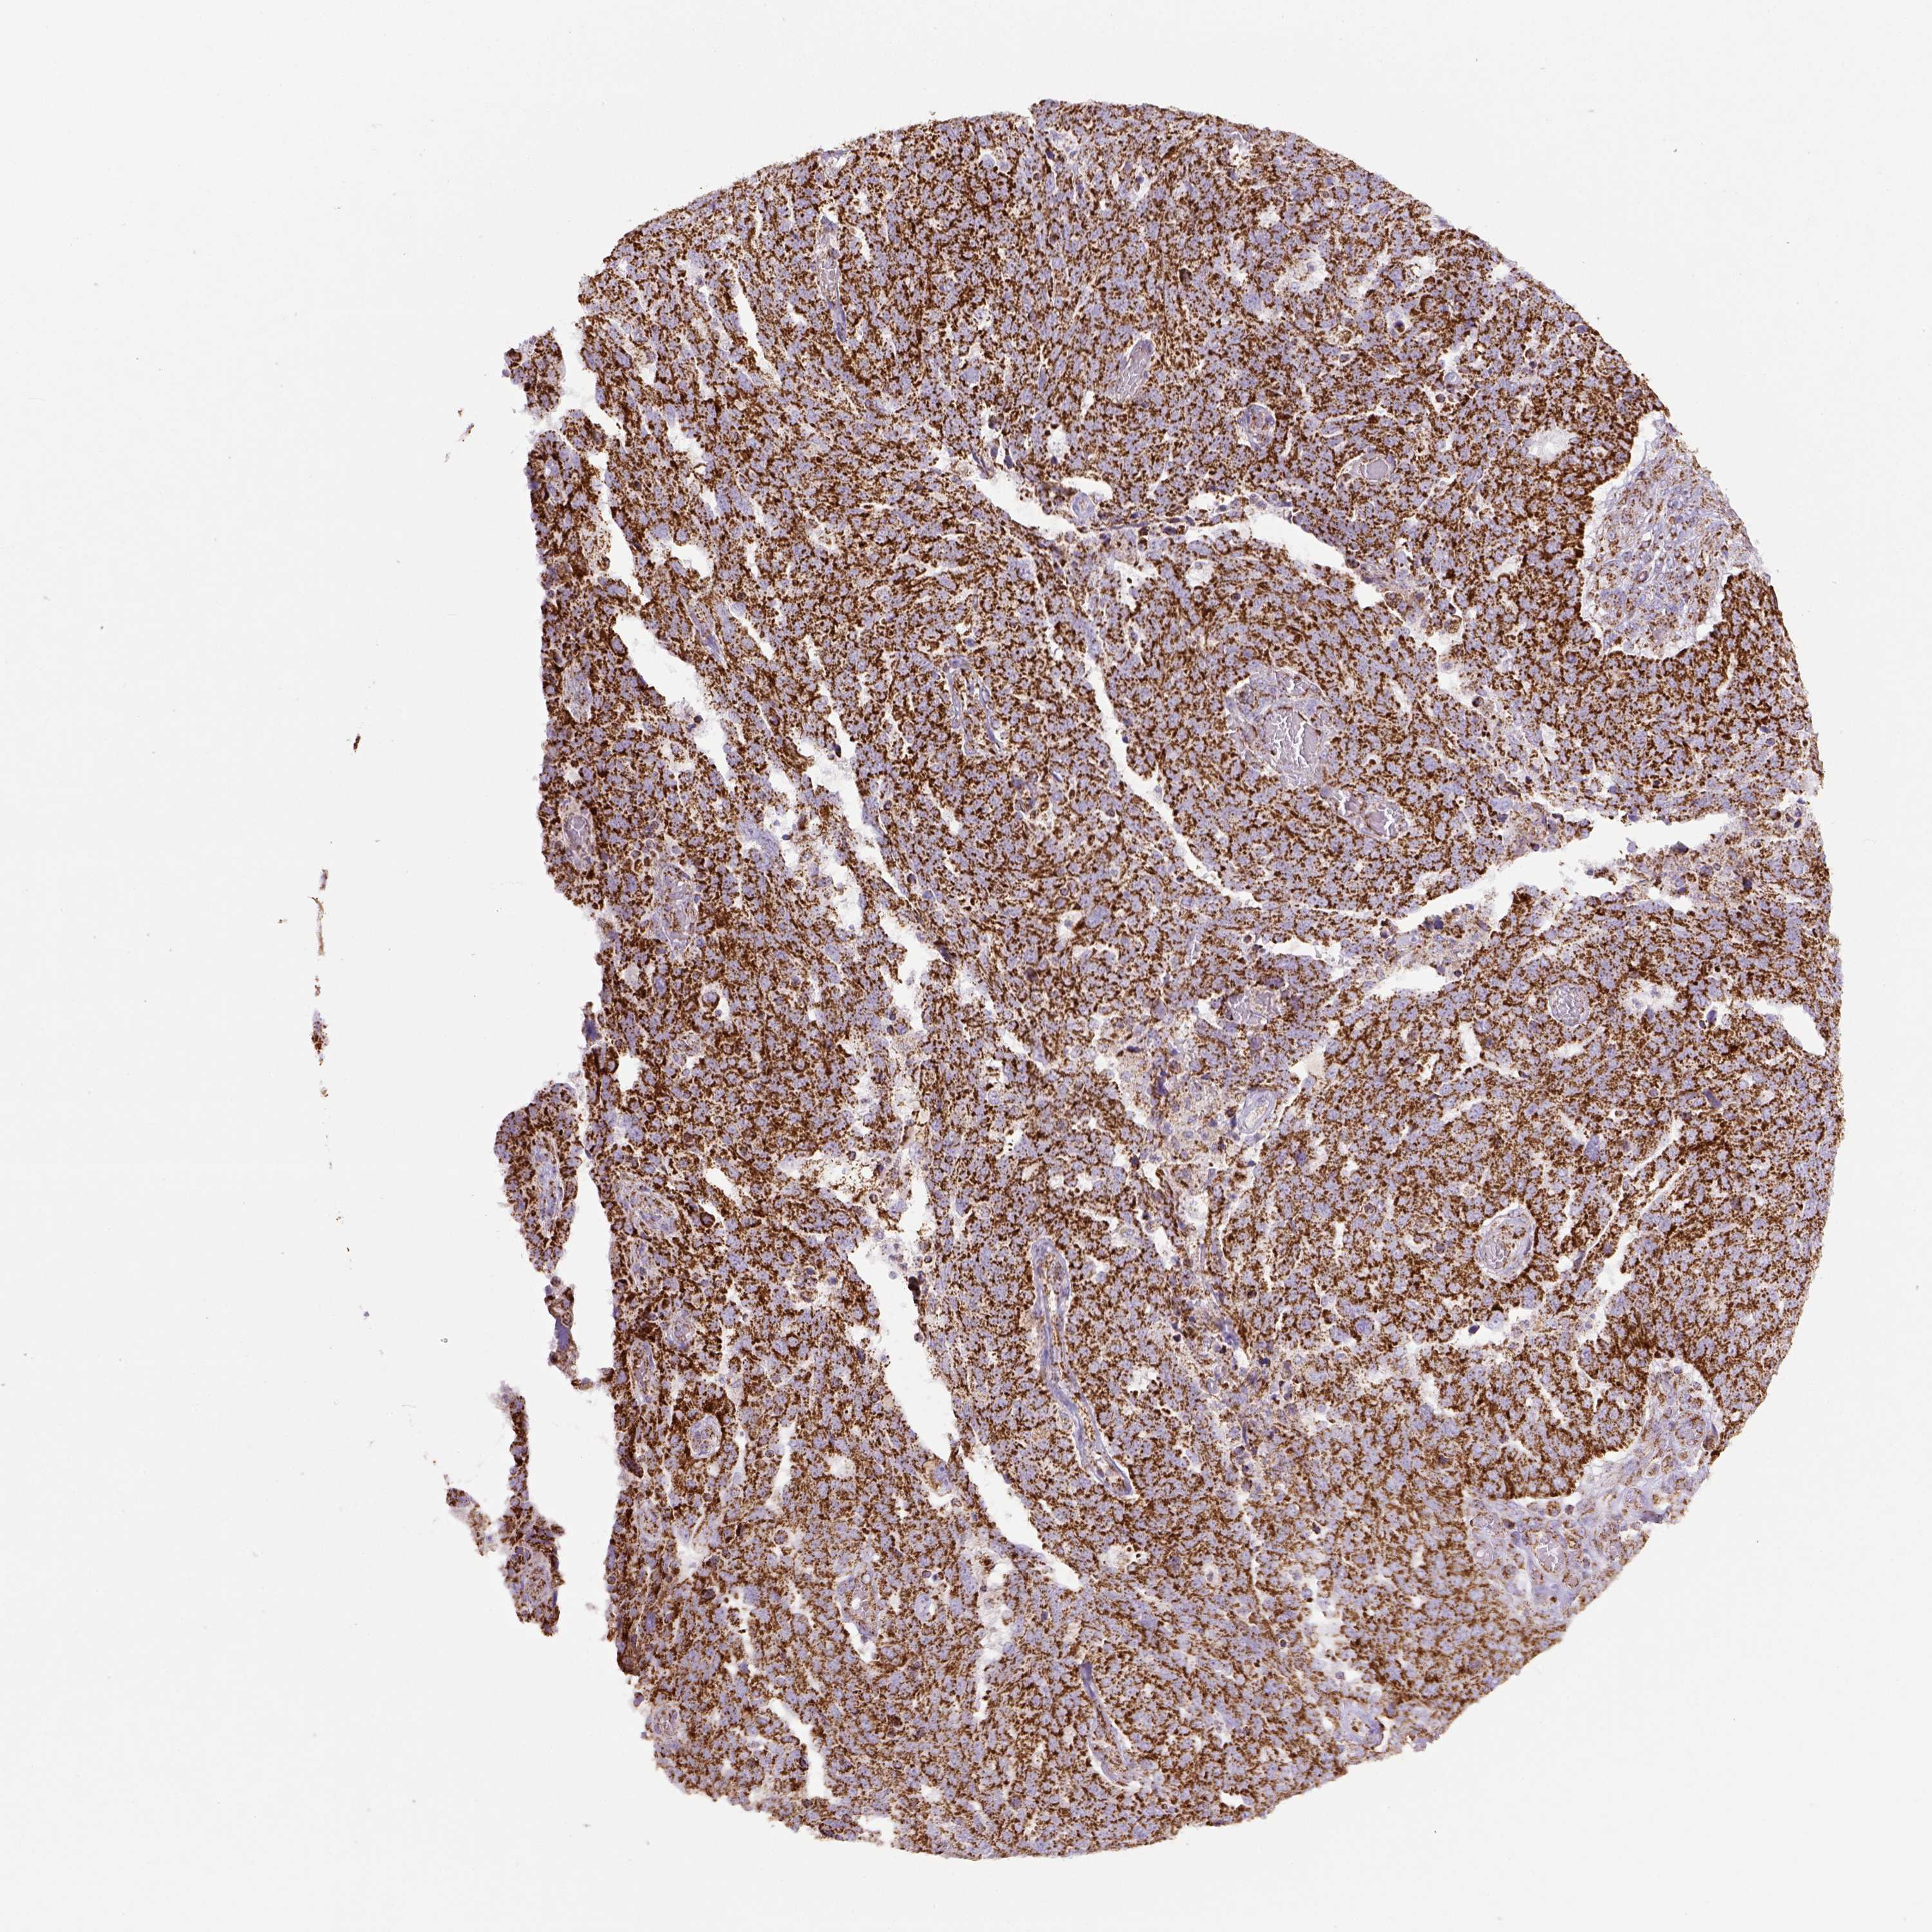

OVARIAN CANCER - Protein expressioni

A mouse-over function shows sample information and annotation data. Click on an image to view it in a full screen mode. Samples can be filtered based on level of antibody staining by selecting one or several of the following categories: high, medium, low and not detected. The assay and annotation is described here.

Note that samples used for immunohistochemistry by the Human Protein Atlas do not correspond to samples in the TCGA dataset.

Antibody stainingi

Antibody staining in the annotated cell types in the current human tissue is reported as not detected, low, medium, or high, based on conventional immunohistochemistry profiling in selected tissues. This score is based on the combination of the staining intensity and fraction of stained cells.

Each image is clickable and will lead to virtual microscopy that enables deeper exploration of all samples and also displays staining intensity scores, fraction scores and subcellular localization as well as patient and tissue information for each sample.

Antibody HPA069328

Antibody CAB016241

Cystadenocarcinoma, serous, NOS

Cystadenocarcinoma, mucinous, NOS

Carcinoma, endometroid